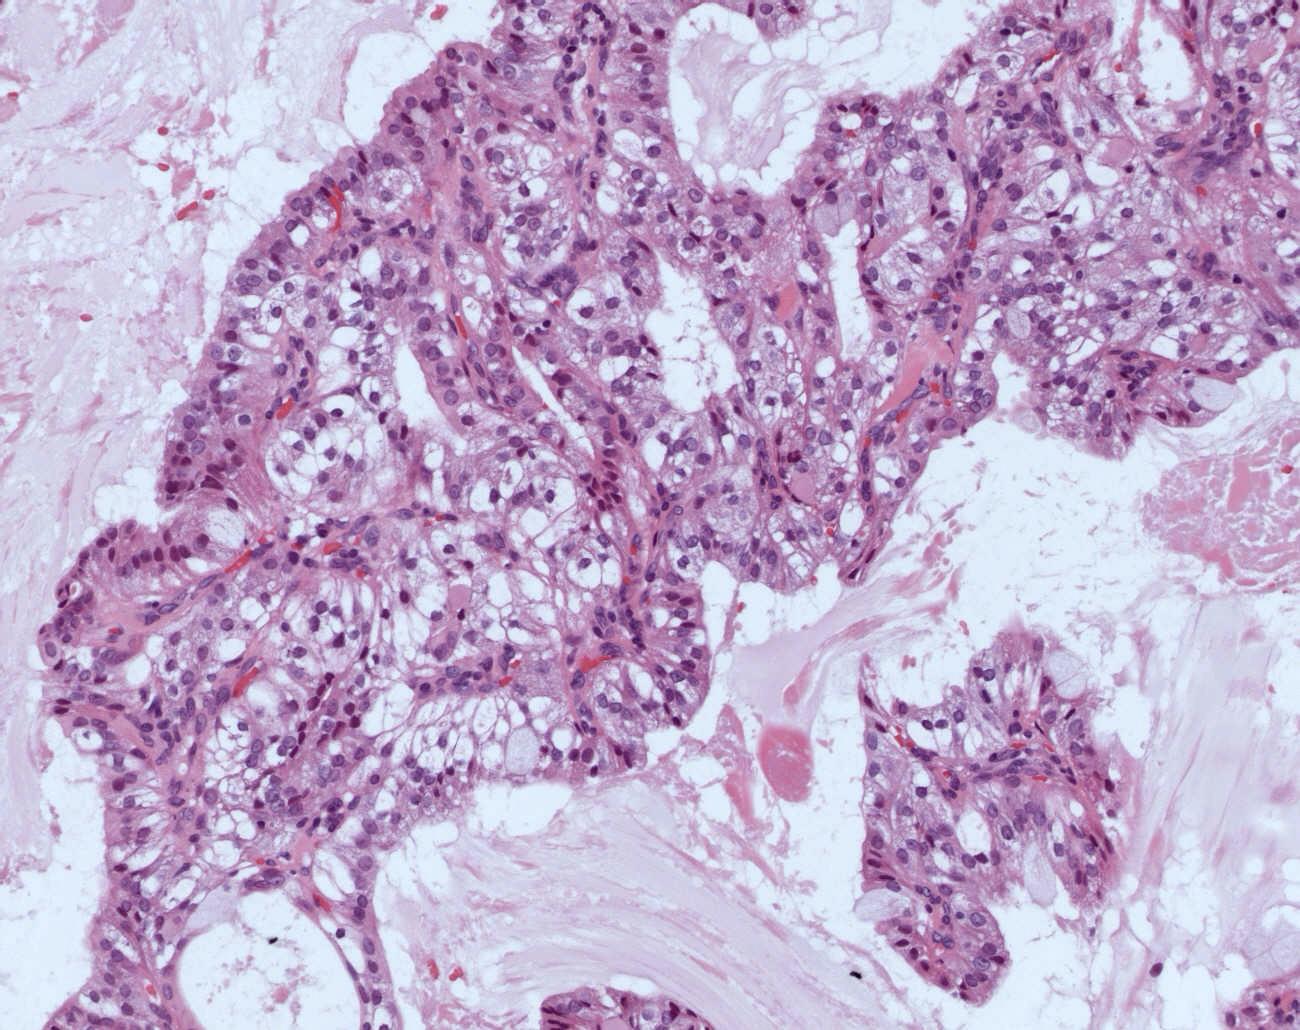

Acinic cell carcinoma

 90% parotid

 Low grade tumour, usually fairly well circumscribed

 Lymphoid stroma

 Variable histological appearances and rarity account for difficult in diagnosis in many cases

In it’s simplest form

Sheets of large polygonal cells with abundant granular basophilic cytoplasm, small eccentric nuclei with even chromatin pattern

Often nested organoid pattern

Other cell

types

 Clear cells

 Non-specific glandular cells

 Hobnail cells

 Vacuolated

 Architectural arrangements

Solid

Papillary cystic

Microcystic

Follicular